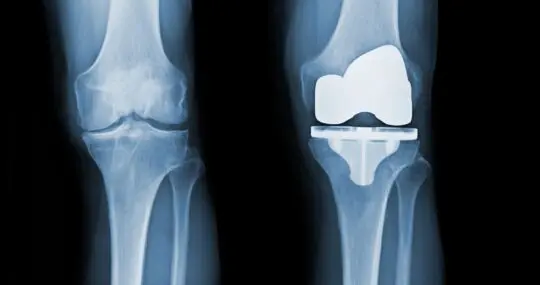

W Szpitalu Carolina przeprowadzamy operacje wymiany stawów kolanowych oraz biodrowych. Wykorzystujemy innowacyjne implanty, indywidualnie dopasowane do potrzeb każdego pacjenta. Przeprowadzamy także operacje rewizyjne.